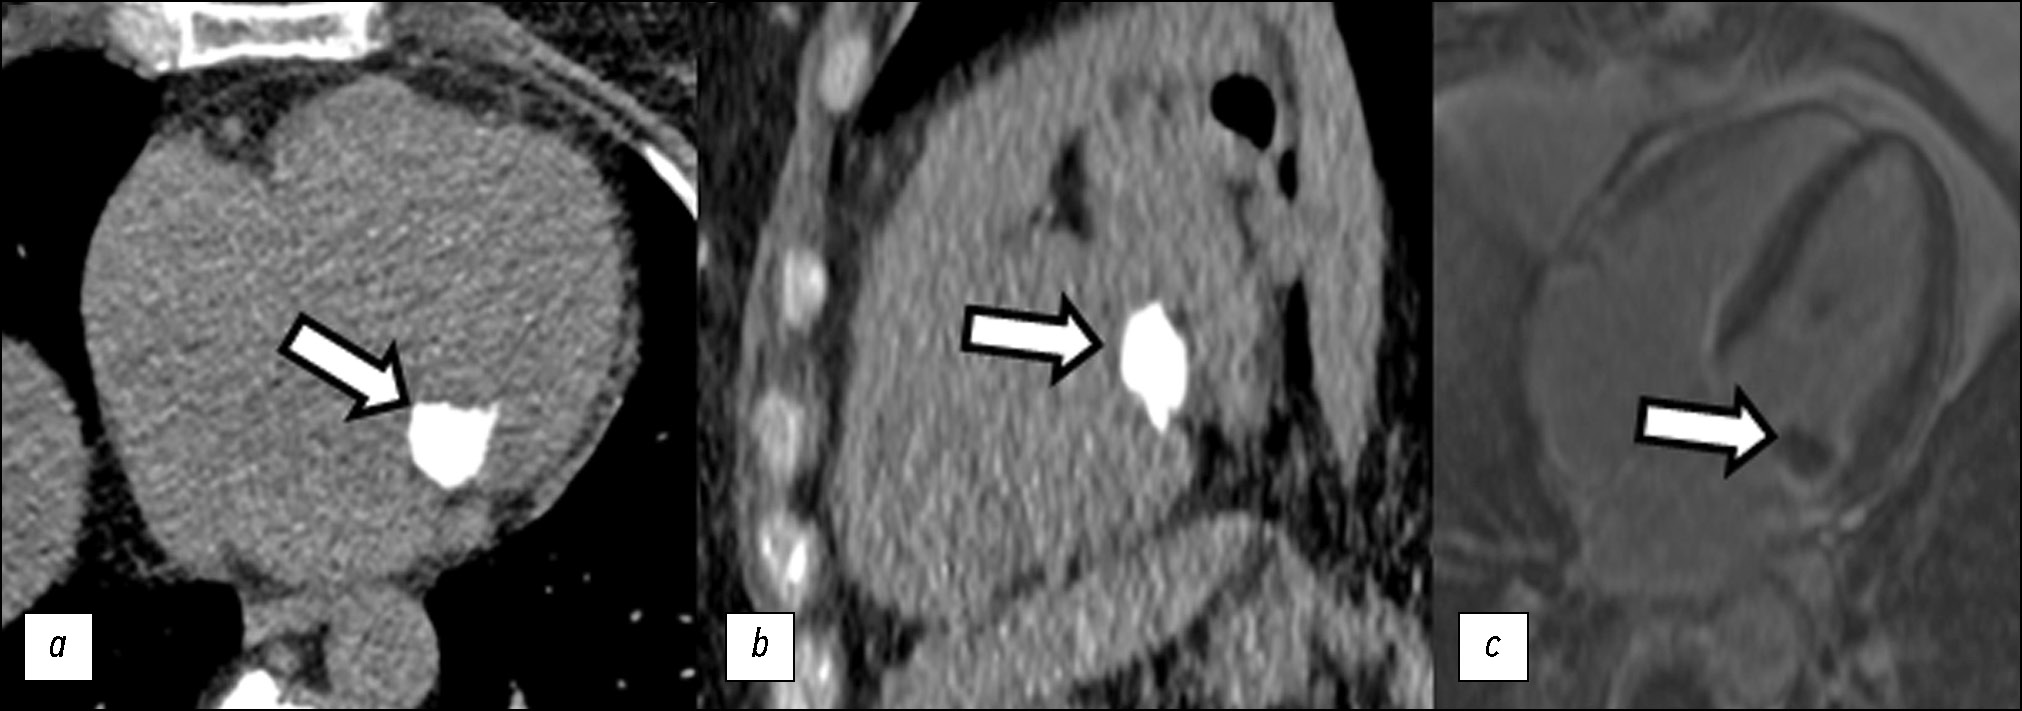

MVC typically has a decreased signal on standard cine MRI sequences, which sometimes makes it difficult to distinguish between calcium, adjacent cardiac muscles, and neoplasms in this location. T2-weighted images make it easier to differentiate MVC from other surrounding structures. Contrast enhancement does not result in significant perfusion during the early phase or delayed enhancement during the late phase (Fig. 2c). A thin rim of contrast is sometimes observed along the margin during the late phase. MVC can be distinguished from benign or malignant neoplasms based on the absence of vascularization and necrosis in the central part. MVC is displayed as a hypointense central part on T1- and T2-weighted images, whereas myxoma and lipoma are characterized by a hypointense signal due to mucin or fat in the stroma [40]. MR signs of abscesses depend on the stage; however, they are typically visualized as structures with a hypointense signal in the center and a hypointense signal in the periphery. However, the sensitivity and specificity of MRI are not always sufficient for an accurate differential diagnosis among MVC, thrombosis, and tumors. In these cases, CT is employed for follow-up examination.

Fig. 2. Female patient, aged 65 years. Mitral valve calcification according to various methods: (a, b) computed tomography (axial and sagittal planes, without contrast enhancement); (c) magnetic resonance imaging (four-chamber long-axis view, delayed contrast enhancement).

On CT, MVC is visualized as a hyperdense structure without signs of contrast uptake, with an avascular, “soft” center. A fibrous capsule with heterogeneous, dense calcium areas is sometimes observed in the periphery [41] (Fig. 2a, b). CT allows determining the location and extent of MVC and its effect on valve function. Calculating the CCS enables a quantitative assessment of MVC.